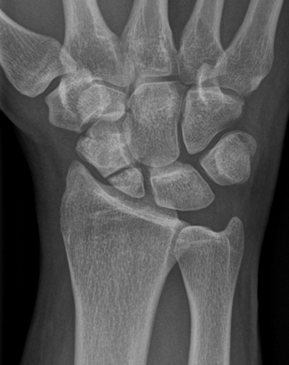

Kahnbeinpseudoarthrose | Vorher

Falschgelenkbildung, sog. Pseudarthrose, bei nicht erkanntem Kahnbeinbruch. Es bestehen deutliche Schmerzen unter Belastung, jedoch liegt noch keine Gelenksabnützung vor.

Kahnbeinpseudoarthrose | Nachher

OP – und Ausheilungsbild nach Anfrischung der Pseudoarthrose, Spongiosaplastik mit Eigenknochen aus dem Beckenkamm, sowie Verschraubung mittels Doppelgewindeschraube. Die Ausbildung einer Gelenksabnützung kann hierdurch verhindert werden.